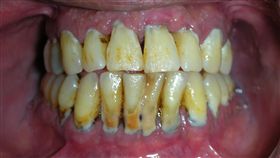

咧嘴驚見殭屍牙?牙醫:問題出在這

您身邊有這種人嗎?一張開嘴就傳來口臭,滿口牙結石、牙...